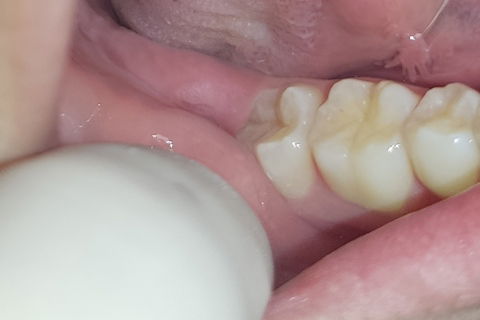

Região do 37/38